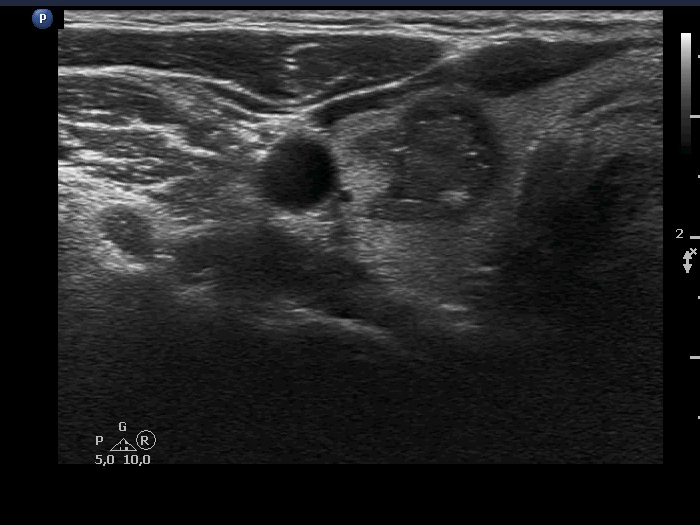

The composition of the nodulen - case 399 (ultrasonographic picture 8)

Right lobe, another transverse scan - after the removal of 2.5 mL cystic content. Note a hyperechoic small patch in the dorsal part of the nodule.